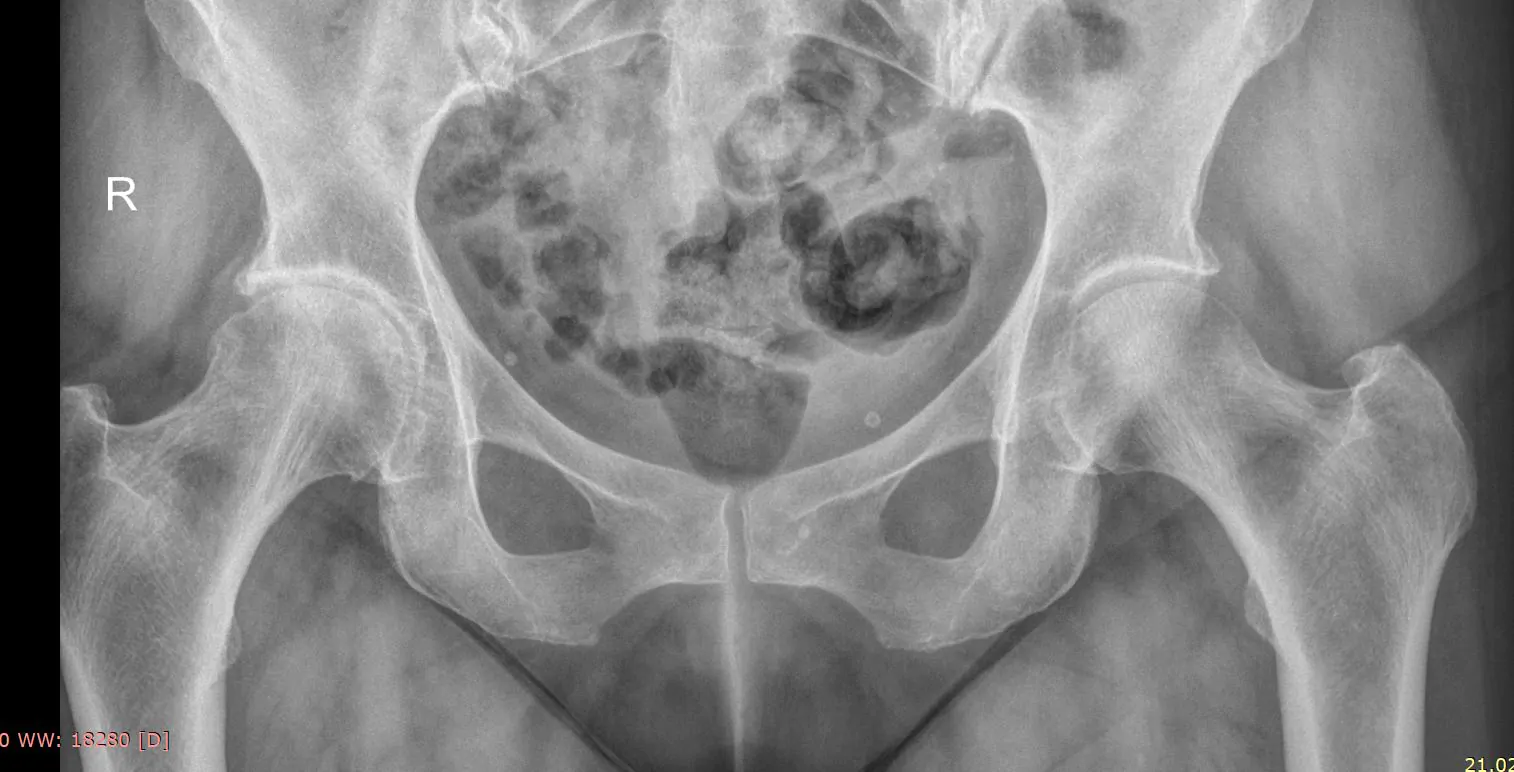

Рентген тазобедренного сустава

Рентген тазобедренного сустава — одно из основных исследований для диагностики травм и заболеваний опорно-двигательного аппарата, выяснения причин боли и нарушений подвижности. Позволяет оценить состояние костной ткани, увидеть места повреждений при вывихе или переломе, дегенеративные процессы и опухоли, выявить различные пороки развития (например, дисплазия тазобедренного сустава).